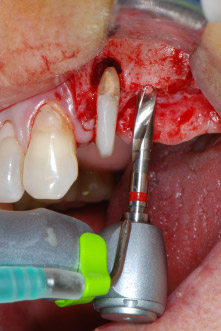

However, we maintained our initial plan to retain both teeth as temporary bridge abutments during the six-months osseointegration period of the implants. At reentry, the situation would have to be reassessed. First, in an attempt to manage the endo-perio problem, the remaining root surface was carefully debrided with piezoelectric equipment (Piezomed, W&H, used with the spatula-shaped insert S1, originally designed for erosion of the lateral sinus wall) (Fig. 4).

IImplant beds were prepared at sites 25 and 26 with rotary instruments, used in a contra-angle handpiece with a 20 : 1 transmission ratio with an updated powerful implant motor (Implantmed, W&H) (Fig. 8).